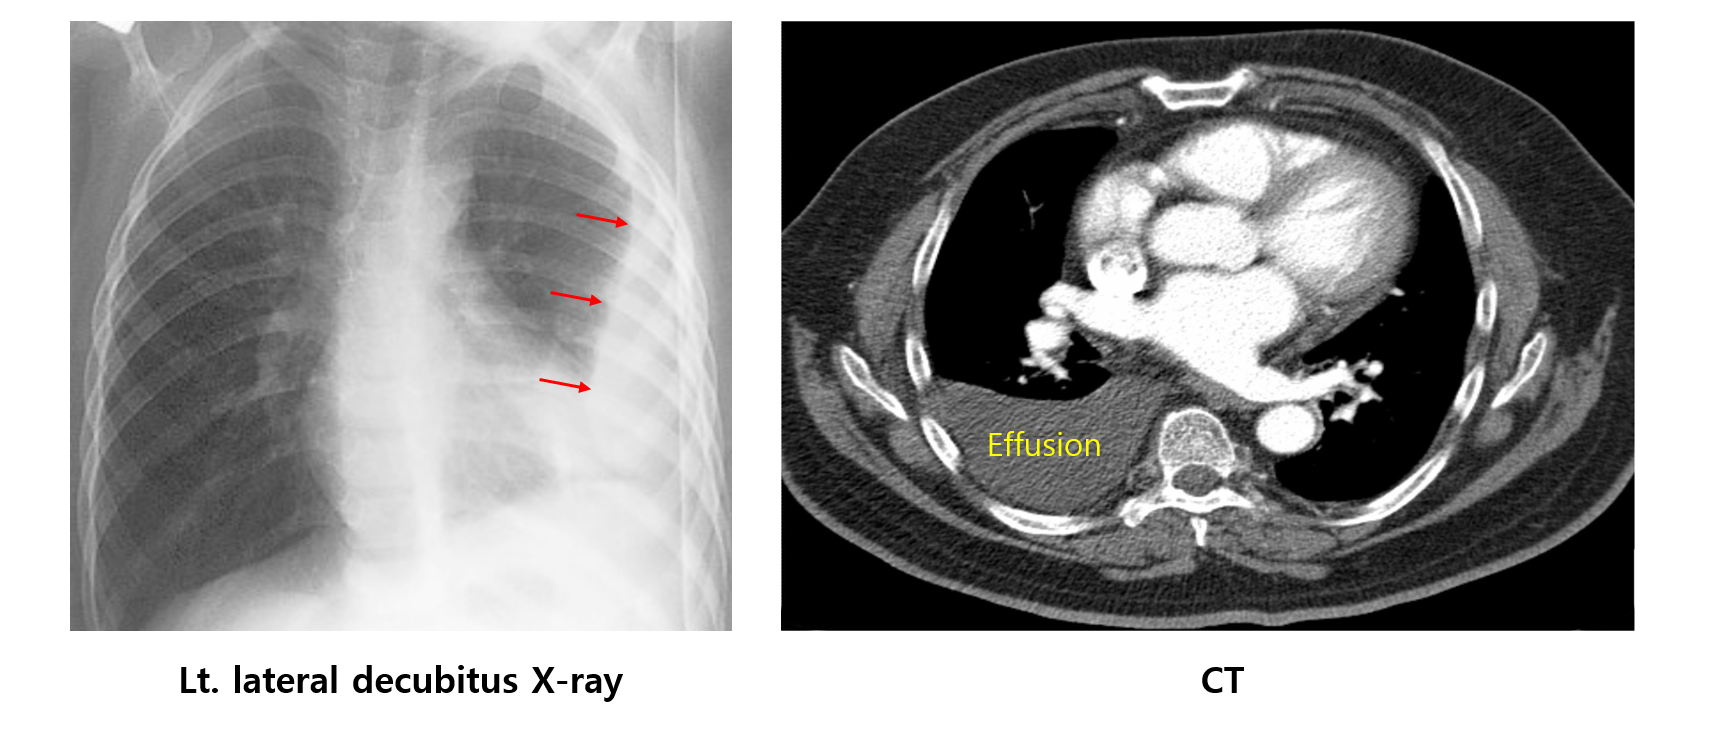

(1) 흉수의 존재 확인

측와위(옆누움, lateral decubitus) CXR

흉부 CT: 흉수의 존재, 원인 질환 등 파악

흉부 초음파: 최근 측와위 CXR을 대신하여 흉막 삼출 진단 및 천자에 사용됨

*Harrison 21e 2197p: Chest ultrasound has replaced the lateral decubitus x-ray in the evaluation of suspected pleural effusions and as a guide to thoracentesis.